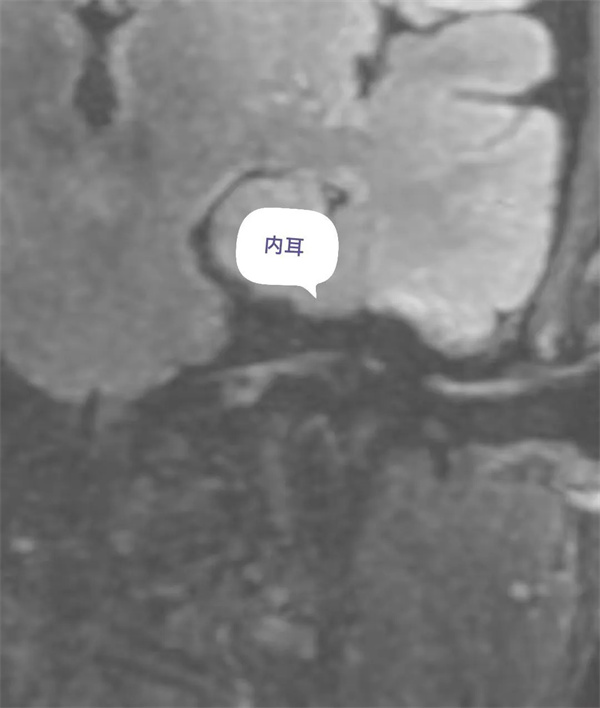

圖11:增強(qiáng)前磁共振內(nèi)耳圖。